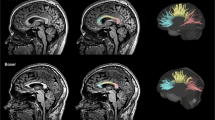

Each set of 3D MPRAGE images was converted from digital imaging and communication in medicine (DICOM) into Neuroimaging Informatics Technology Institute (NIFTI) format and uploaded onto the pipeline volBrain (https://volbrain.upv.es) [22]. It is based on the following preprocessing steps: denoising using the spatially adaptive non-local-means (SANLM) filter [23], coarse inhomogeneity correction [24], registration to Montreal Neurological Institute (MNI) space [25], fine inhomogeneity correction using statistical parametric mapping (SPM) [26], intensity normalization [27]. After that, further steps follow to aid the estimation of brain volumes at different scales: non-local intracranial cavity extraction (NICE) [28], tissue classification [29], non-local hemisphere segmentation (NABS) [30] and non-local subcortical structure segmentation [31].

For this investigation we measured total intracranial volume (TIV), defined as the sum of intracranial grey matter (GM), white matter (WM) and cerebrospinal fluid (CSF), normalized brain volume (NBV), defined as the sum of GM and WM divided by TIV, as well as deep grey matter volumes of the thalamus, globus pallidus, putamen, caudate nucleus, nucleus accumbens and amygdala, respectively. Volume values for both sides were added.

For statistical analysis of the deep grey matter, these structures were set into reference to head size by dividing the volume of the structure by NBV, analogous to the methods used in Ward et al. [32] as presented in Fig. 1. Deep grey matter structures were compared between the boxer and HC groups by applying a multivariate analysis of variance with BMI. Our results were also corrected for effects of age in an analysis of covariance. Linear regression analysis examined the association between number of fights and duration of boxing in years on regional brain volumes of boxers.